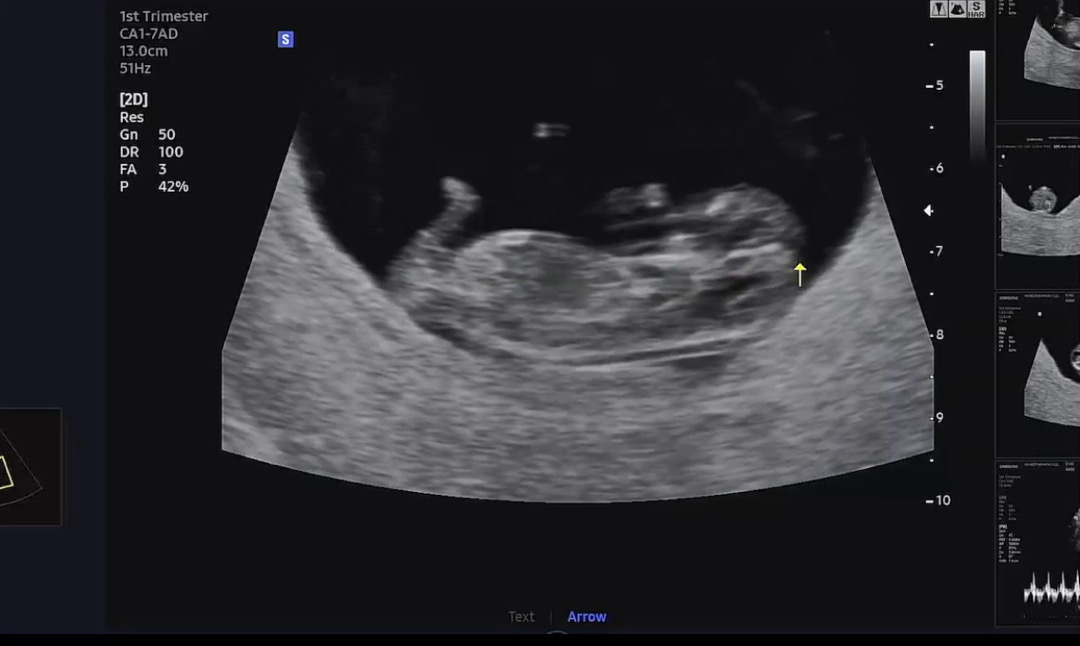

안녕하세요~ 11주차 예비맘입니다!오늘 드뎌 복부로 초음파 보구왔는데요 혹시나 성별을 알 수 있나해서요 ㅎ 전 둘 다 너무 감사하지만 그래도 궁금하긴하네용! 여기 계신분들 다 건강하게 아가들 만나시길 바라요😀